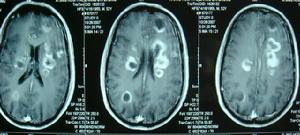

3.CT掃描:不但可定位,並可顯示腫瘤的大小、形狀及腦組織、腦室的改變、特別易於發現多發性腫瘤、腫瘤類圓形或形狀不規則,呈高密度或混雜密度影像,混雜密度者常為腫瘤內有壞死囊變,則顯示有低密區。強化後大多有明顯的塊狀或環狀影像增強、腫瘤周圍常有低密度腦水腫帶。可見腦室受壓變形,小腦腫瘤可見第三腦室以上對稱擴大。